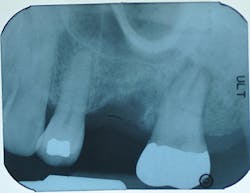

2-D periapical image

3-D imaging

Root fracture as seen on an axial scan view. Clinical photos courtesy Dr. Bradley McAllister, DDS, PhD